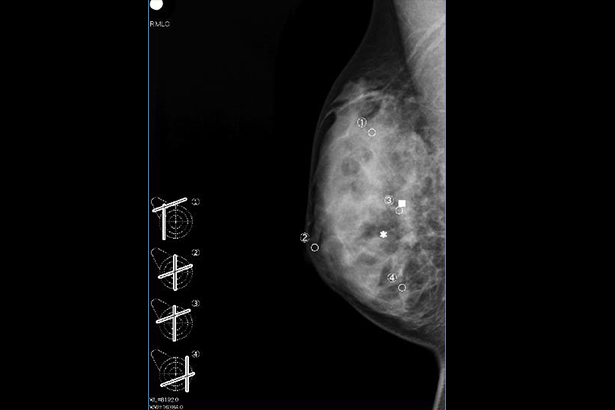

在超聲設備上,在乳腺 X 線攝影 MLO/CC 圖像上指定病變的位置,就可以在乳腺的超聲圖像上標記病變的估計位置。